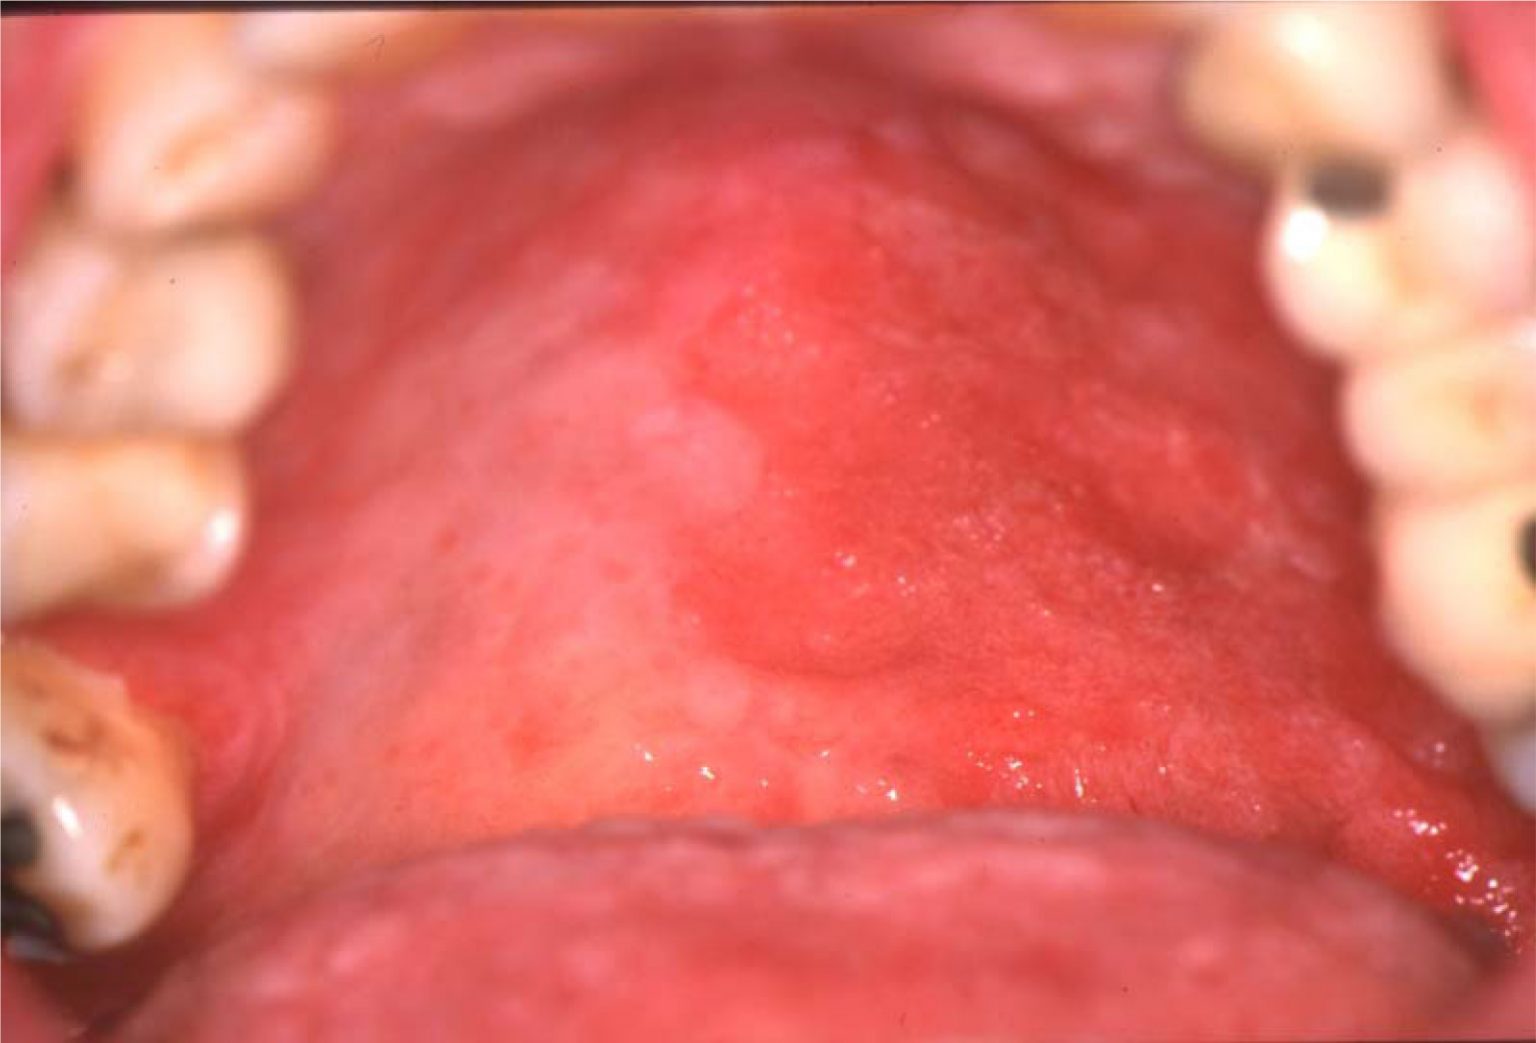

Roof of the mouth after a gum graft What to expect? Oral Skin Graft A gum graft, also called a gingival graft, is a periodontal surgery that corrects receding gums. Gum grafting covers exposed teeth roots and adds volume to your gum line, improving overall oral health. Gum graft surgery (also called a gingival graft or periodontal surgery) covers exposed tooth roots caused by receding gums. A gum graft might refer to a few. Oral Skin Graft.

Graft Versus Host Disease European Association of Oral Medicine Oral Skin Graft The first sign of root exposure is typically sensitivity to hot and cold substances. A gum graft, also called a gingival graft, is a periodontal surgery that corrects receding gums. A gum graft, also known as a gingival graft, can correct receding gums. A gum graft might refer to a few different procedures, but all of them involve putting new. Oral Skin Graft.

Why Does My Gum Graft Look Gray? Oral Skin Graft A gum graft, also known as a gingival graft, can correct receding gums. It is a quick and relatively simple surgery in which a periodontist removes healthy. Gum graft surgery (also called a gingival graft or periodontal surgery) covers exposed tooth roots caused by receding gums. Skin grafting can be of great use in the orofacial region and should be. Oral Skin Graft.